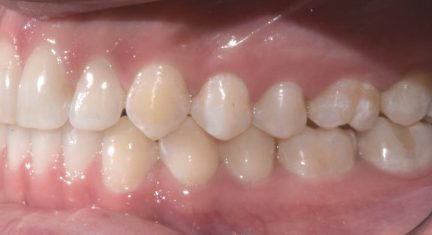

Classe I, arcades étroites, chevauchement, espacement, diastème

- Option de traitement Invisalign: Invisalign Lite

Durée totale du traitement

- 4 mois

Nombre d'aligners

- Maxillaire: 14

- Mandibulaire: 14

État initial